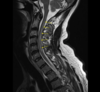

- MRI spine: spinal cord lesions

- Serial gadolinium-enhanced MRI

- MRI spine T2